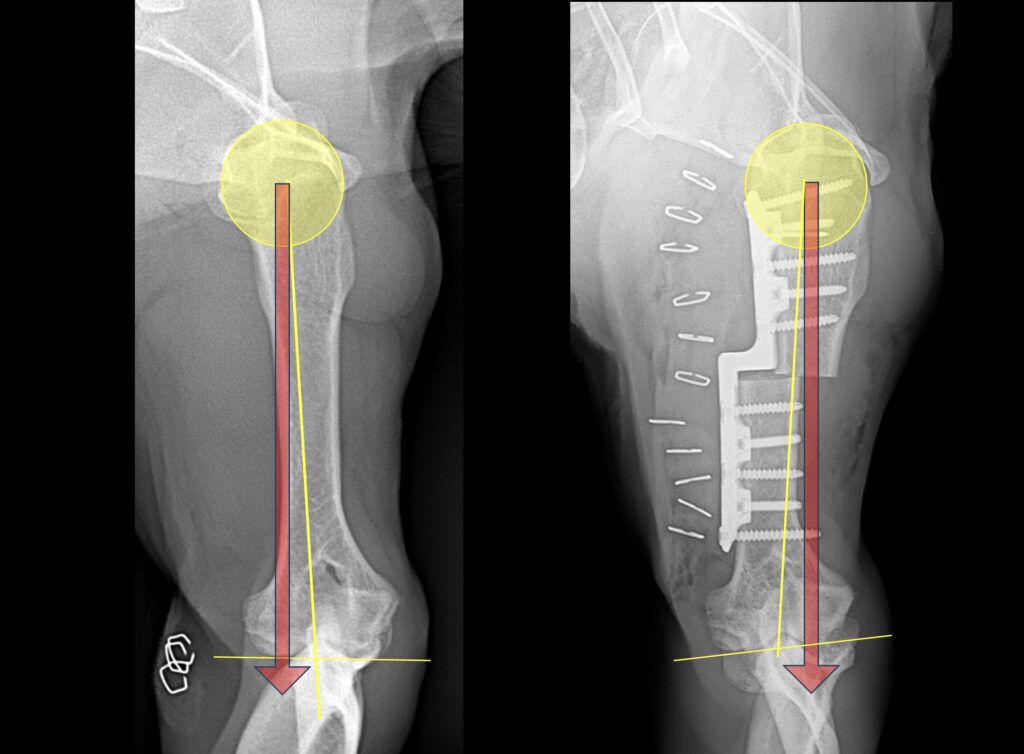

Předložená série pacientů popisuje soubor 15 psů s různými formami onemocnění mediálního kompartmentu loketního kloubu. Pro přenos zátěže z mediálního na laterální kompartment loketního kloubu byla využita metoda Sliding Humeral Osteotomy (SHO). Celkem bylo operováno 20 končetin. Ve všech případech bylo provedeno klinické vyšetření, rentgenologické vyšetření, vyšetření celých končetin počítačovou tomografií (CT) a artroskopické vyšetření postižených loketních kloubů. Článek stručně popisuje techniku SHO, pooperační režim a komplikace. U sedmi pacientů byly z důvodů malé velikosti využity individuálně vyrobené SHO implantáty. U všech ostatních pacientů se jednalo o standardní velikosti plotének. Závažné komplikace byly pozorovány ve dvou případech. U jednoho pacienta došlo k přelomení implantátu druhý týden po zákroku. Druhý pacient vykazoval rentgenologické změny odpovídající atrofii kosti v místě osteotomie dvanáctý týden po zákroku. Ke kompletnímu zhojení osteotomie došlo u všech pacientů do dvanácti týdnů. Biometrická analýza chůze prokázala u většiny studovaných pacientů plnohodnotnou funkci nerozlišitelnou od normálu, a to většinou do dvanácti týdnů po zákroku. V jednom případě byla provedena pět měsíců po zákroku kontrolní artroskopie, která prokázala rozsáhlou regeneraci mediálního kompartmentu fibrotickou chrupavkou. I přes technickou náročnost zákroku se jeví metoda jako velice úspěšná a zvláště v případě mladých pacientů s mediální osteochondrózou ji lze považovat za kurativní zákrok.

The presented retrospective case series describes a group of 15 patients with various forms of medial compartment disease of the elbow joint. The Sliding Humeral Osteotomy (SHO) method was used to transfer the load from the medial to the lateral compartment of the elbow joint. A total of 20 limbs were operated on, in all cases clinical examination, radiological examination, examination of the entire limbs by computed tomography (CT) and arthroscopic examination of the affected elbow joints were performed. The article briefly describes the SHO technique, postoperative management and complications. In seven patients customized SHO implants were used due to the small size of the dogs, in all other patients, standard size plates were used. Major complications were observed in two cases, in one patient the implant failed in the second week after the procedure due to excessive activity of the dog, another patient showed radiological changes corresponding to bone atrophy due to stress protectionat the osteotomy site in the twelfth week after the procedure. Complete healing of the osteotomy occurred in all patients within twelve weeks. Biometric gait analysis demonstrated a full function indistinguishable from normal in most of the studied patients, mostly within twelve weeks after the procedure. In one case, a follow-up arthroscopy was performed five months after the procedure, which demonstrated extensive regeneration of the medial compartment with fibrotic cartilage. Despite the technical complexity of the procedure, the method appears to be very successful and, especially in the case of young patients with medial osteochondrosis, it can be considered a curative procedure.*